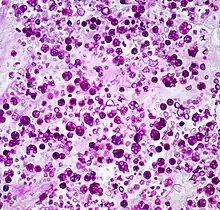

| Histologic stain of a Prototheca zopfii infection in a dog | |

Protothecosis, otherwise known as Algaemia, is a disease found in dogs, cats, cattle, and humans caused by a type of green alga known as Prototheca that lacks chlorophyll and enters the human or animal bloodstream. It and its close relative Helicosporidium are unusual in that they are actually green algae that have become parasites.[1] The two most common species are Prototheca wickerhamii and Prototheca zopfii. Both are known to cause disease in dogs, while most human cases are caused by P. wickerhami.[2] Prototheca is found worldwide in sewage and soil. Infection is rare despite high exposure, and can be related to a defective immune system.[3] In dogs, females and Collies are most commonly affected.[4]

Prototheca has been thought to be a mutant of Chlorella, a type of single-celled green alga. However, while Chlorella contains galactose and galactosamine in the cell wall, Prototheca lacks these. Also, Chlorella obtains its energy through photosynthesis, while Prototheca is saprotrophic, feeding on dead and decaying organic matter. When Prototheca was first isolated from slime flux of trees in 1894, it was thought to be a type of fungus.[6] Its size varies from 2 to 15 micrometres.[7]

In dogs

Disseminated protothecosis is most commonly seen in dogs. The algae enters the body through the mouth or nose and causes infection in the intestines. From there it can spread to the eye, brain, and kidneys. Symptoms can include diarrhea, weight loss, weakness, inflammation of the eye (uveitis), retinal detachment, ataxia, and seizures.[11]

Dogs with acute blindness and diarrhea that develop exudative retinal detachment should be assessed for protothecosis.[6] Diagnosis is through culture or finding the organism in a biopsy, cerebrospinal fluid, vitreous humour, or urine. Treatment of the disseminated form in dogs is very difficult, although use of antifungal medication has been successful in a few cases.[4] Prognosis for cutaneous protothecosis is guarded and depends on the surgical options. Prognosis for the disseminated form is grave. This may be due to delayed recognition and treatment.[3]